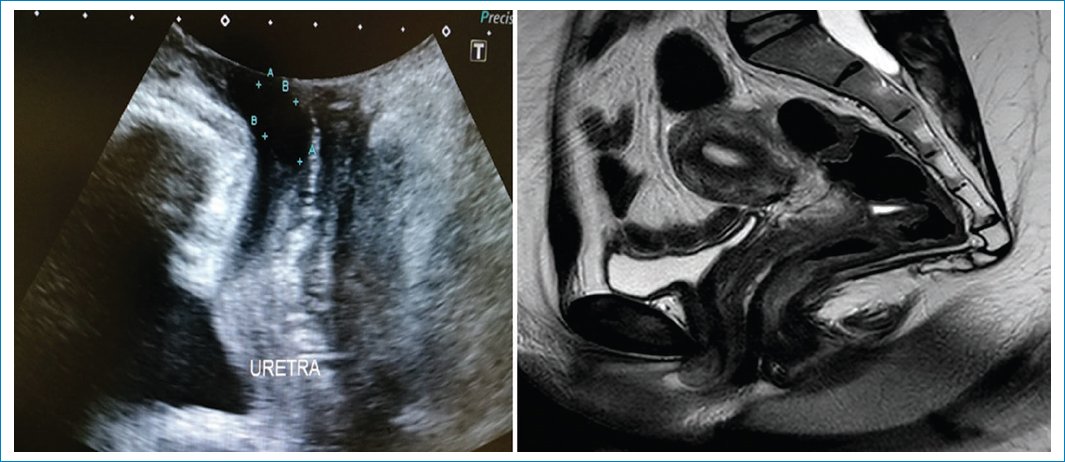

Figura 5. En la ecografía se observa una lesión hipoecoica en la luz uretral. En la RM se identifica una lesión levemente hiperintensa en secuencia sagital T2 que protruye hacia el meato uretral externo, en relación con un pólipo fibroepitelial confirmado por anatomía patológica.

Figura 6. Se observa la medición del descenso del cuello vesical durante reposo y Valsalva.